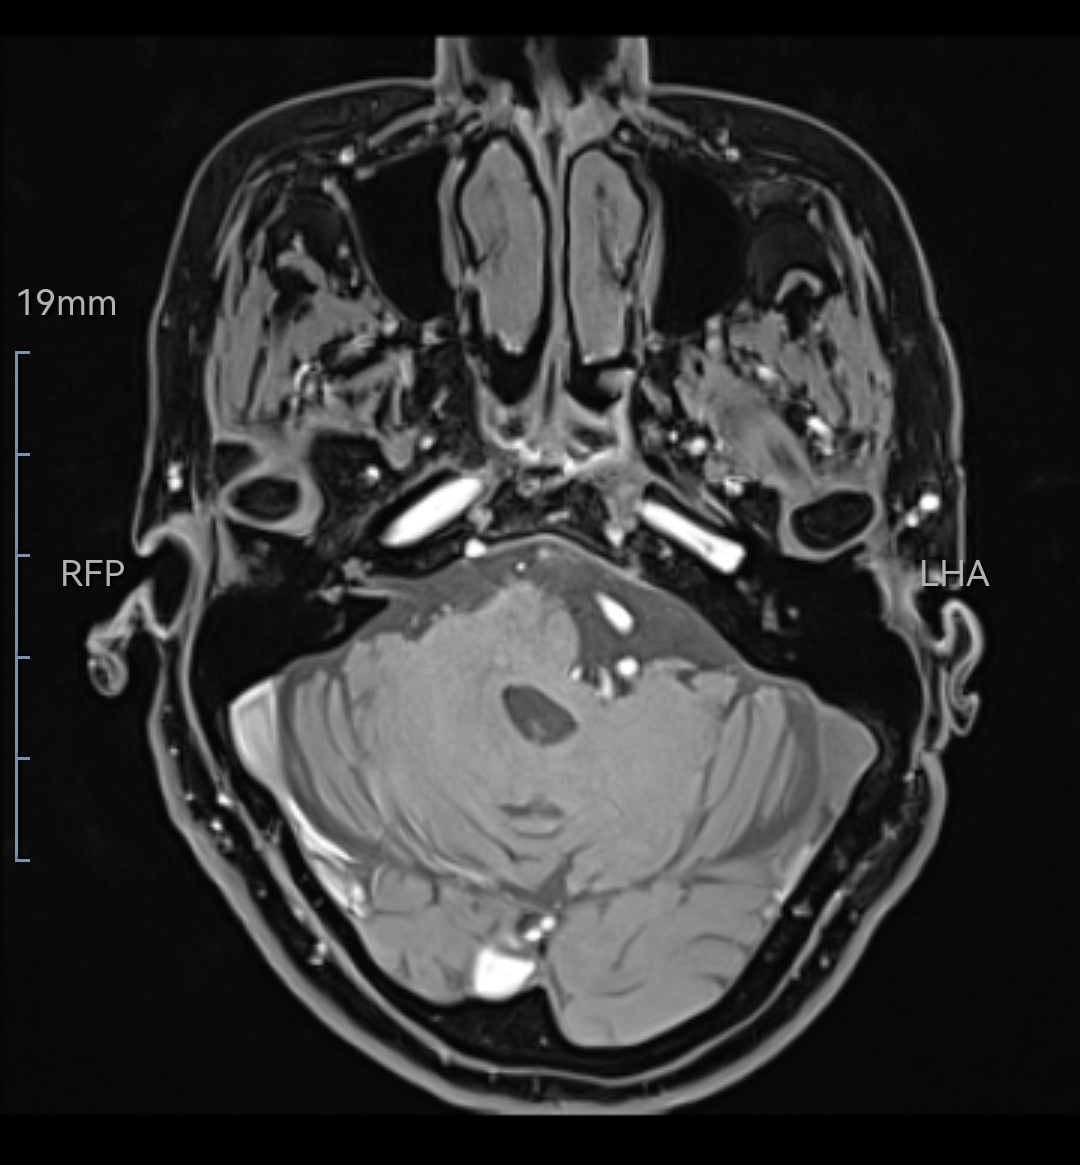

现病史:71岁女性,左侧咽后壁针刺样疼痛10余年,喝水吃饭吞咽动作可以诱发疼痛。近2月疼痛加重,不能忍受。服卡马西平出现头晕手脚麻木。

既往史:8年前在外院诊断为左侧舌咽神经痛,2016年外院行微血管减压术,术后疼痛缓解4年后复发。复发后做过射频消融术、局部阻滞,均无效。

诊断:左侧舌咽神经痛(术后复发)